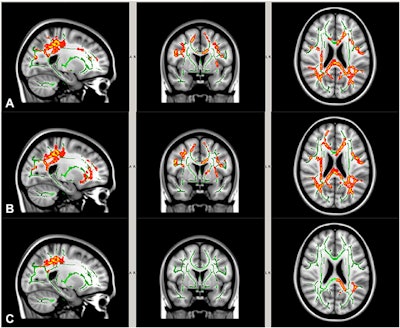

A comparison of DTI scans from the preseason to season's end showed reductions in axial diffusivity among both groups in specific brain regions. Interestingly, however, the high school group "demonstrated greater white-matter microstructure changes than the youth football group, as evidenced by more widespread axial diffusivity reduction," which was contrary to the authors' hypothesis, they noted.

After adjusting for the number and severity of head impacts, the researchers found the average reduction in axial diffusivity was significantly greater among high school football players than the younger players -- the high school players had approximately a 2.5% reduction in axial diffusivity, compared with a reduction of 0.4% in the younger athletes (p < 0.05).

The group observed significant reductions among the high school athletes in the corpus callosum, anterior and posterior limbs of the internal capsule, corona radiata, and superior longitudinal fasciculus, among other regions. The junior high school footballers showed significant reduction in more limited regions, including the anterior corona radiata, superior corona radiata, and external capsule.